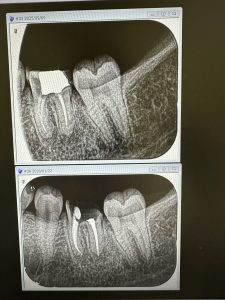

次の喜びは、歯性上顎洞炎

大した病巣ではないが、小さい内に芽を摘む

4か月経過。本日根充

次は下6番の根充、4ヶ月経過

これも大したインパクトは無いが、昨年から大臼歯には白水のエンドシェーパー、グライダーを拘り使用

モリタの専用コントラ、800回転 1Nで使用

非常に楽、特に上のエンド3角、湾曲根管にはベスト